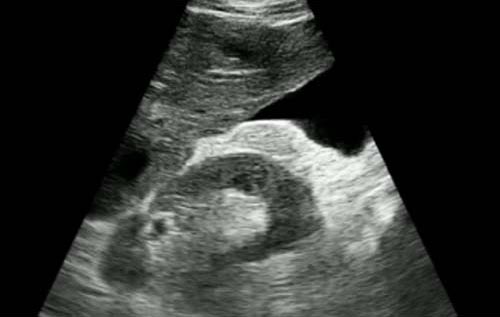

Semana 12

Paciente 30 anos IC prévia, hepatopata, com COVID confirmado. O que podemos ver na imagem?